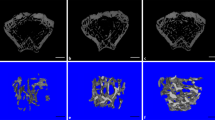

Tartrate-resistant acid phosphatase (TRAP) stain in proximal tibial growth plates of control (C; a) and rapamycin-treated (RAPA; b) animals. Magnification bars: 100 μm

Picrosirius red/alcian blue/hematoxylin staining of proximal tibial growth plates of control (C; a) and rapamycin-treated (RAPA; b) animals with details of the structure of the primary trabeculae. Magnification bars: 100 μm

Vascular endothelial growth factor (VEGF) immunohistochemical stain counterstained with methyl green in proximal tibial growth plates of control (C; a) and rapamycin-treated (RAPA; b, c, d) animals. Magnification bars: 100 μm

Vascular invasion front and primary spongiosa

Dispersed TRAP-positive elements (chondroclasts/osteoclasts) were found in septa of the primary spongiosa and along the vascular invasion front in the two groups of rats (Fig. 6). Direct examination under the microscope showed that TRAP-positive elements at the chondro-osseous junction had a somewhat regular distribution in C animals (Fig. 6a)—approximately one every three terminal chondrocytes. In the same area of RAPA samples (Fig. 6b), fewer and irregularly distributed TRAP-reactive cells were seen. The number of TRAP-reactive cells per 100 terminal chondrocytes in RAPA samples (18.7 ± 0.5) was less than that of controls (31.0 ± 0.8).

Picrosirius red/alcian blue staining highlighted morphological and structural differences in the primary spongiosa of both groups (Fig. 7). Thin longitudinal septa, parallel to the long axis of bone, defined the primary spongiosa in control animals (Fig. 7a). These longitudinal trabeculae, built on a nucleus of cartilage matrix-blue–covered by a thin layer of bone matrix-red (insert in Fig. 7a)–marked the path of invading capillary sprouts. The longitudinal arrangement of septa and vessels was distorted in RAPA samples (Fig. 7b) by the presence of transverse unresorbed septa made of cartilage and/or bone matrix. As opposed to the slender structure of primary trabeculae found in control animals, thicker trabeculae, including empty rings of cartilage or bone matrix, were often seen in the primary spongiosa of treated animals (insert in Fig. 7b).

Immunohistochemistry for VEGF

VEGF immunohistochemical signal was intracellular and localized within the cytoplasm of hypertrophic chondrocytes in the control group (Fig. 8a). In RAPA animals, no uniform pattern for VEGF immunostaining was seen (Fig. 8b–d). In some cases, VEGF immunostaining was indistinguishable from that seen in controls (Fig. 8b). In other samples, VEGF signal was found irregularly dispersed in the hypertrophic zone, and terminal chondrocytes were rarely immunopositive (Fig. 8c). In some sections, both patterns coexisted in the same sample, particularly in those samples with narrow and widened cartilage zones (Fig. 8d). A regular staining of the hypertrophic zone was generally found in nonexpanded areas of the growth cartilage whereas scanty and dispersed labeled cells were seen in areas of expanded hypertrophic zone.